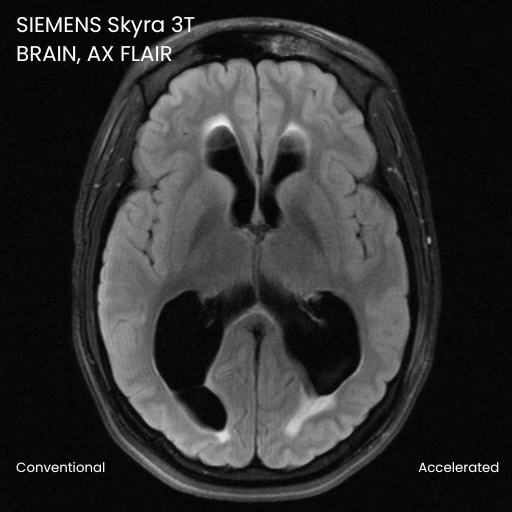

Case Studies

Robarts Research Institute

The evaluation of the effectiveness of DeepFoqus-AccelerateTM for accelerated brain MRI scans.

Accept up to 4x accelerated scans and reconstruct them to yield acceptable scans when compared to standard unaccelerated scans.

*The claim is based on the prospective studies we conducted with radiologists. Results in other cases may vary.14.0 min and 49.02 sec